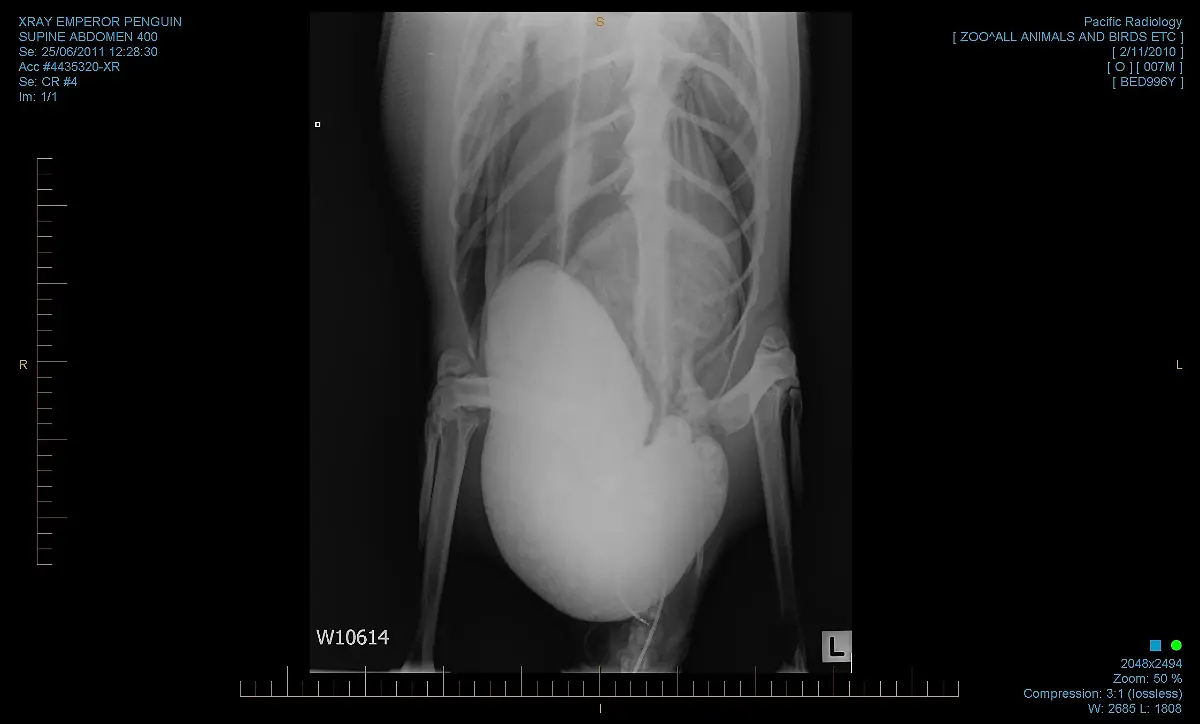

3000 Kilometer von seiner Heimat entfernt taucht ein Pinguin an der Küste Neuseelands auf. Die neue Umgebung bekommt "Happy Feet" nicht. Er ist überhitzt, ausgemergelt und hat Sand im Magen. In einer dramatischen Rettungsaktion kommt er in den Zoo Wellington, wo Ärzte um sein Leben kämpfen.